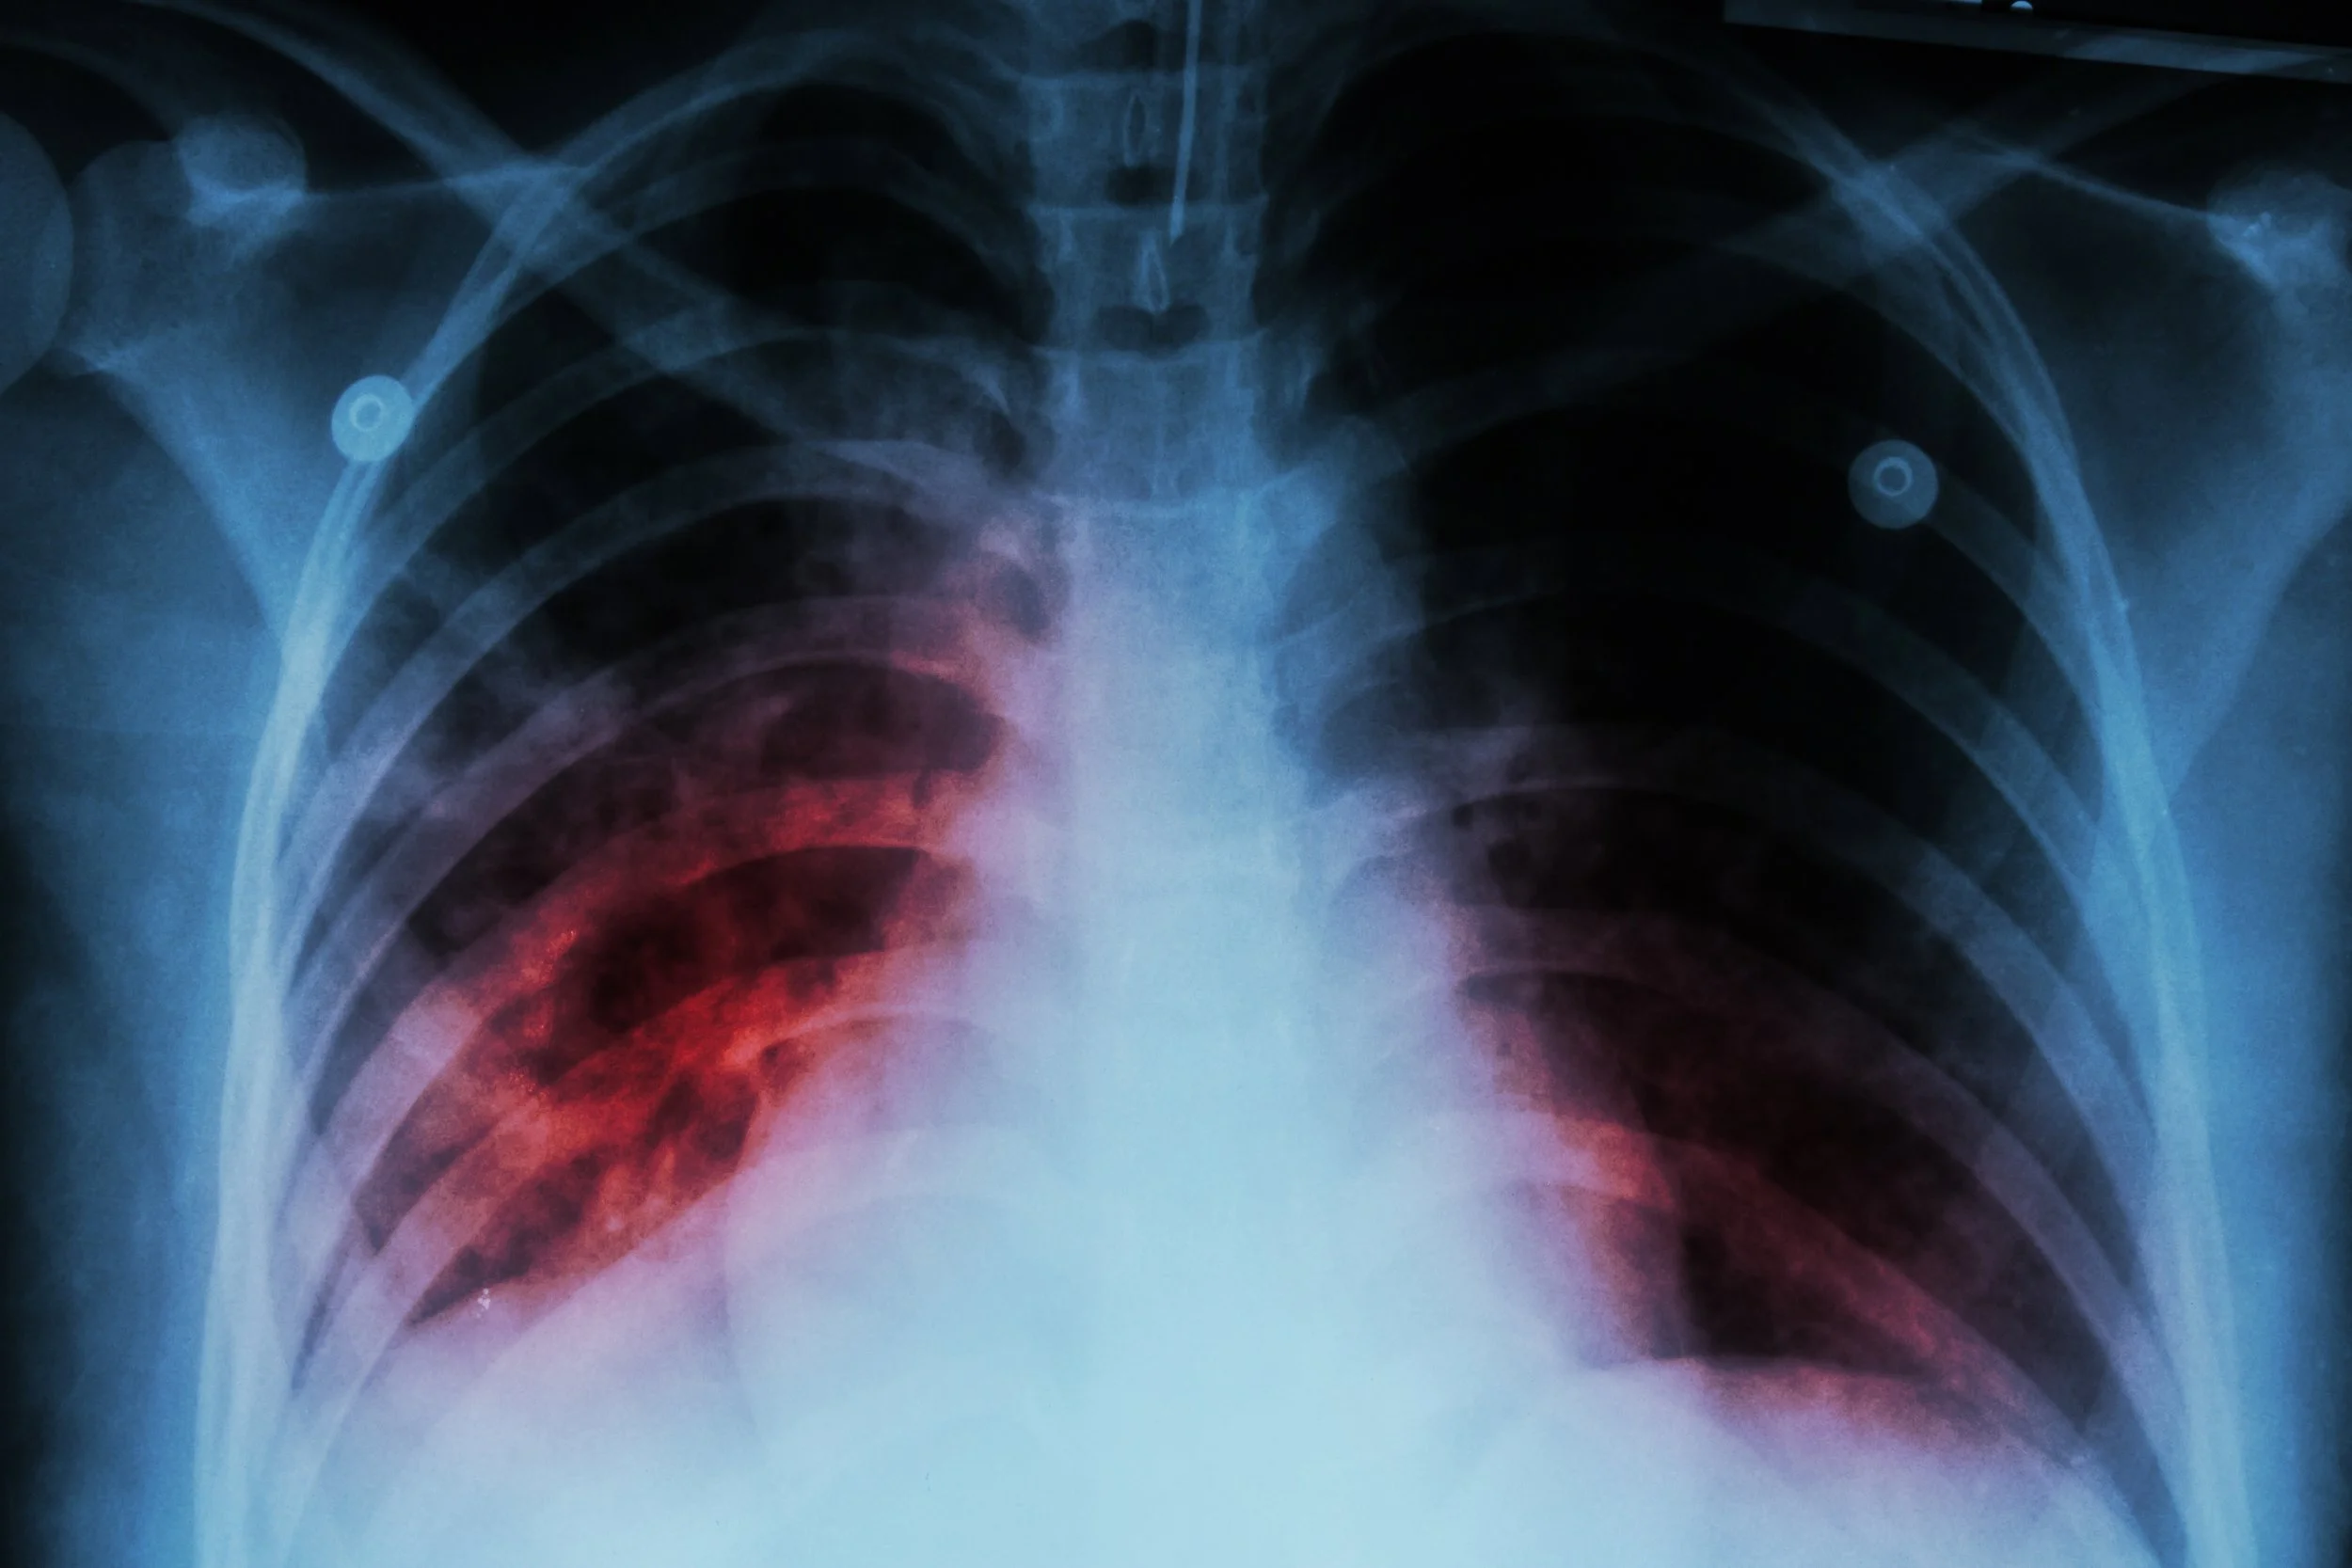

VIRAL ILLNESS headlines Norovirus causes up to 21 million illnesses in the U.S. every year. Here’s what to know about the contagious disease that hand sanitizer can’t kill Measles cases are mounting in the US as the UK declares a ‘national incident’ over the disease. What parents need to know to keep their kids safe pneumonia is the no. 1 cause of hospital admission in kids and adults. watch for these signs and symptoms What is ‘white lung’ pneumonia, and why is it reportedly on the rise in kids? What parents need to know